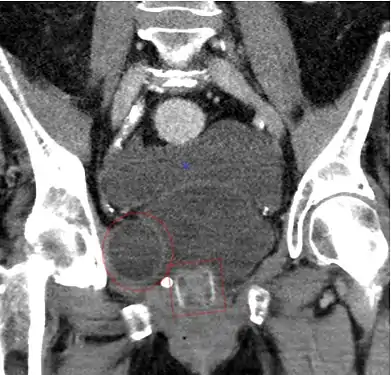

تصوير مقطعي يظهر مصرة AMS 800 عند إمرأة